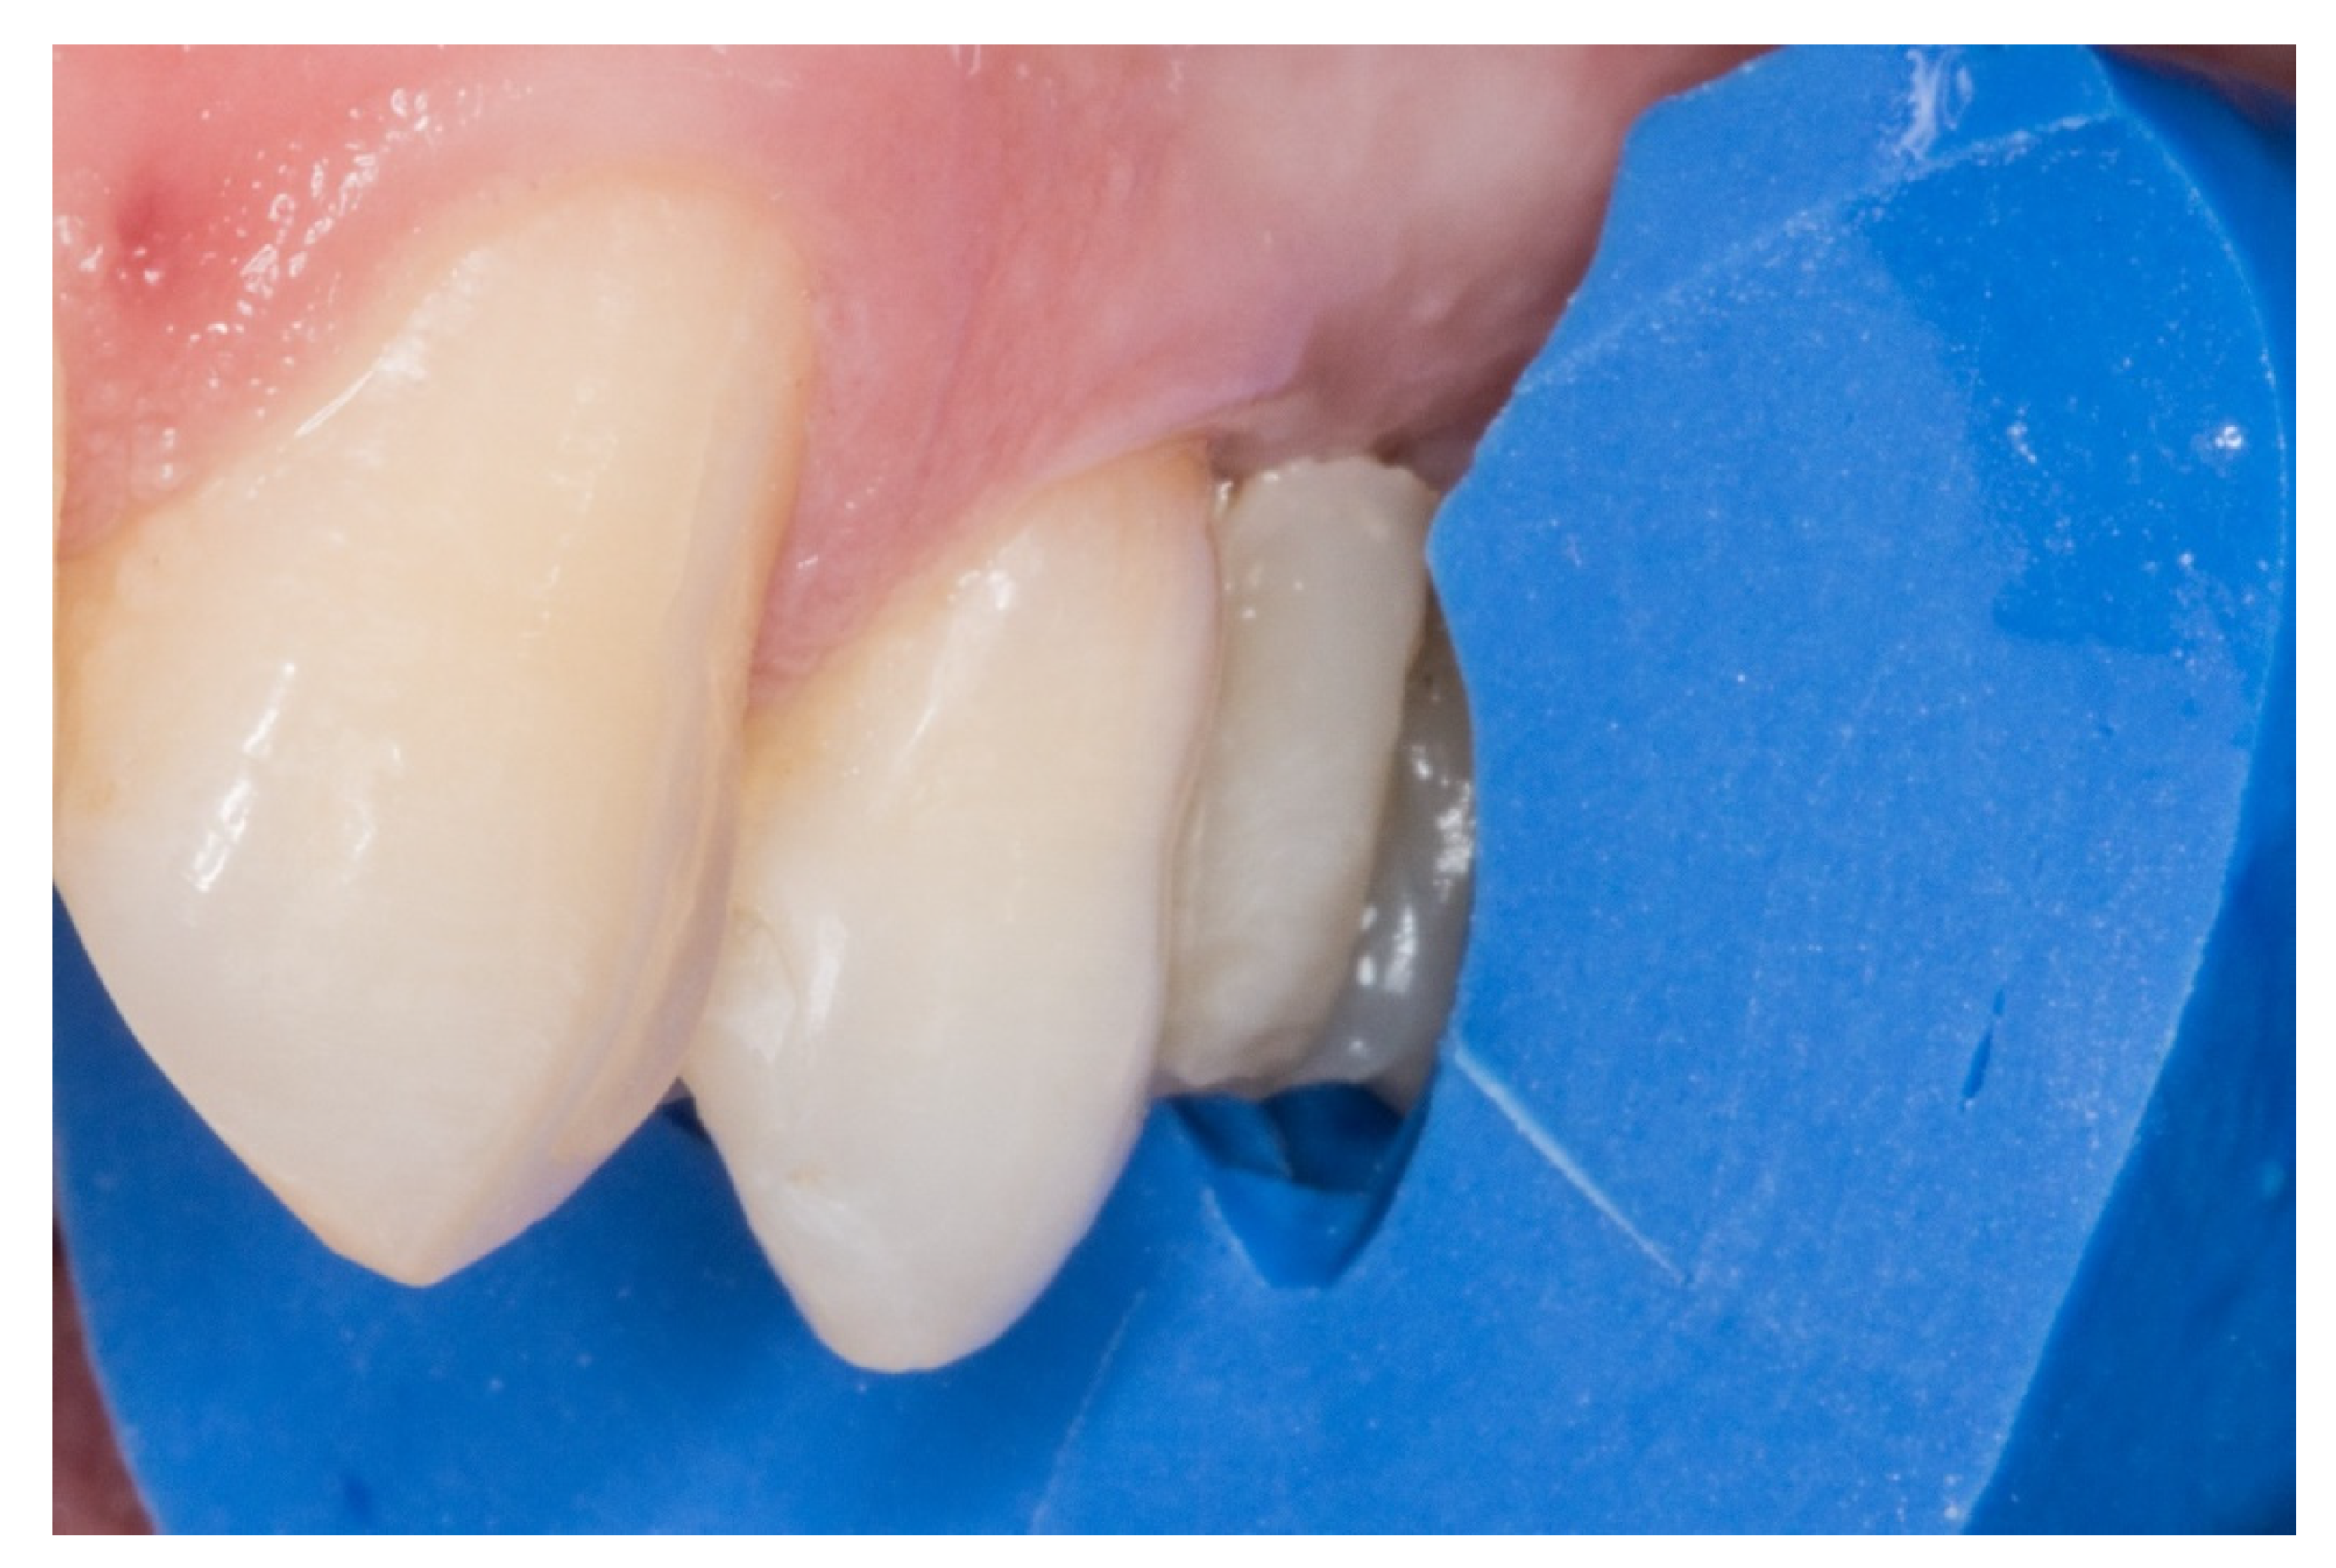

- Long term survival: this proposed protocol which uses inlay retainers and a core with two “T” shaped pins reinforces and stabilizes the FRCB, allowing greater survival over time.